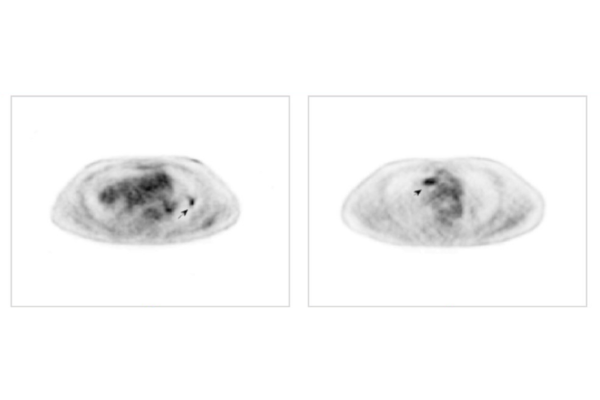

In the paper, Jha, who is also an assistant professor at the university’s Mallinckrodt Institute of Radiology (MIR), and his collaborators, who included physicians, physicists and computational imaging scientists, present two observer-study-based approaches for evaluating the realism of synthetic images: one using a theoretical ideal observer and the other using expert human observers with the aid of an online platform. This tool, which is publicly available through MIR, is already being used by international collaborators in the medical imaging community.

But not all fakes are bad. If scientists can create synthetic medical images that look real enough, those images can be used to conduct virtual clinical trials. Virtual trials can help imaging scientists and physicians develop new imaging techniques while saving time, money and patient exposures. These trials are especially helpful for applications in rare diseases where scientists don’t have enough real cases to perform reliable evaluations of novel imaging methods.